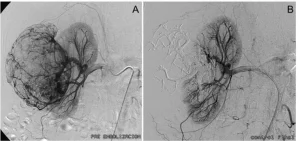

A) Cateterismo de riñón derecho en paciente con angiomiolipoma de 9 cm. B) Después de la embolización el angiomiolipoma ha desaparecido, pero permanecen intactas todas las arterias sanas del riñón tratado.

El tratamiento de los AML se realiza con equipos específicos de radiología llamados angiógrafos digitales que actúan como GPS: permiten identificar adecuadamente dónde debe ir el catéter y tratar de manera muy precisa solo las arterias enfermas del riñón, dejando intactas las arterias sanas. No hay cicatriz, la recuperación es rápida y sin apenas efectos secundarios, y el paciente mantiene el 100% de la función renal.